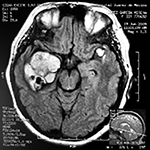

Paciente masculino de 34 años de edad, quien presenta crisis convulsivas parciales motoras de brazo y hemicara derecha, secundariamente generalizadas, posteriormente hemiparesia 4/5 para hemicuerpo derecho.

La TAC muestra un área hiperdensa a nivel frontal izquierdo heterogénea que no refuerza con medio de contraste.

LA RMN muestra una lesión bien circunscrita frontal parasagital izquierda con edema perilesional, hiperintensa en T1 y T2, de contenido sólido y quístico, con poca captación del medio de contraste.

Se realizó craneotomía frontal para abordaje interhemisférico anterior.

Se realiza resección total de la lesión de contenido hemático oscuro-verdoso, consistente en un angioma cavernoso. La RMN postoperatoria se observa solo la brecha quirúrgica sin evidencia de lesión.

En el postquirúrgico el paciente desarrollo síndrome frontal lateral, que se controló con Risperidona y remitió después de tres semanas, las crisis convulsivas remitieron y el medicamento se disminuyó de manera paulatina (figs. 4 y 5).

Imágenes prequirúrgicas y postquirúrgicas de lesión multiloculada del caso 9.